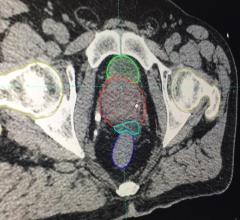

CT Virtual Simulation

This is an example of the Mirada DLCExpert deep learning software that automatically identifies organs, segments and ...